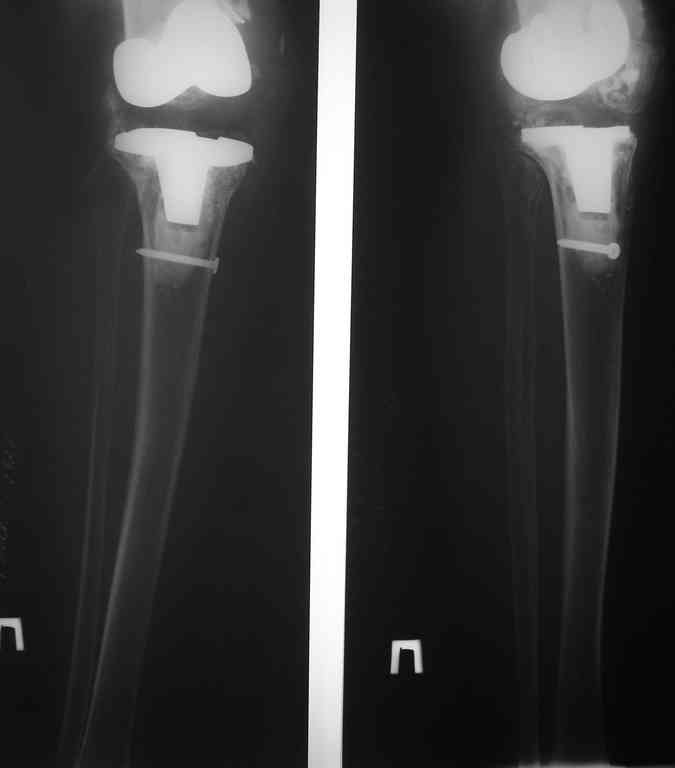

This patient is a 78 y o woman, she has osteoarthritis.3 years ago she had a total right knee replacement (Zimmer LPC).

after she started to walk without a cane,she felt that her knee is (giving way).the clinical knee examination showed medial knee instability and valgus deformation of this knee.2 years ago MCL repair was achieved……and no improvement.A year ago,she had knee replacement for this knee for the second time with bigger-sized implant and no improvement…now she using crutches and knee orthosis. In attachments ,2 monthes ago x-ray images. Any suggestion?